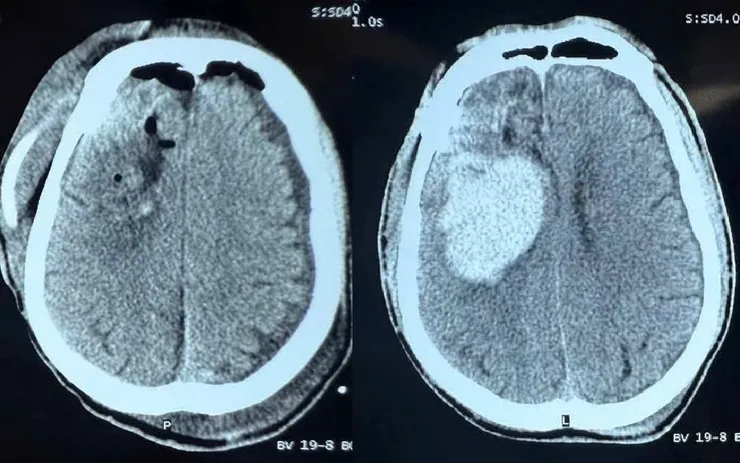

Bệnh nhân nhập viện trong tình trạng lơ mơ, điểm Glasgow 12, liệt nửa người trái. Kết quả chẩn đoán hình ảnh cho thấy bệnh nhân bị xuất huyết não vùng trán - thái dương phải, cần can thiệp phẫu thuật khẩn cấp. Ekip đã tiến hành mổ lấy máu tụ kịp thời nhằm giải phóng chèn ép não, hạn chế nguy cơ tử vong và di chứng nặng.